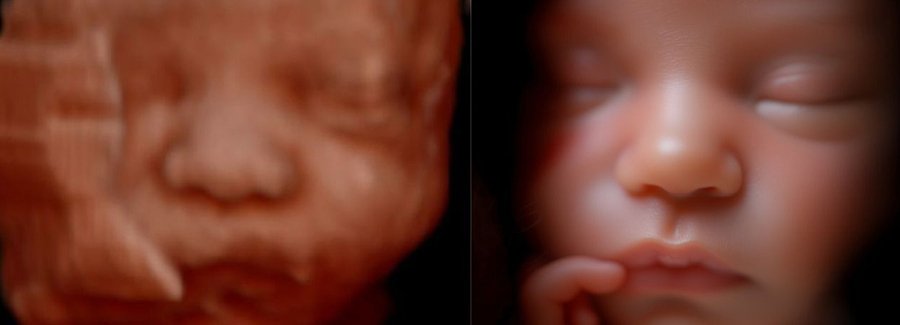

The best time to see your baby’s face in 5D/HD is between weeks 25 and 30 of your pregnancy.

Often referred to as 5D, HD or FRV (fetal realistic view), 5D/HD is the newest development in pregnancy imaging. It captures and combines high definition volume data to create automated images with amazing color and clarity so you can see your baby as though you were looking from inside the womb.